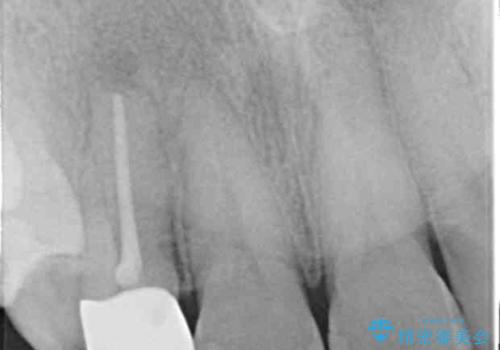

X線検査の結果、失活(感染根管)であることが判明したので、感染根管治療後セラミック補綴を計画します。